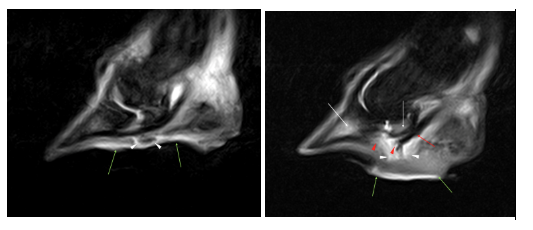

The previously localised interosseous signal on the below sagittal STIR images (previous scan to the left, recent scan to the right) was now diffuse within the distal phalanx and the navicular bone (white arrows), and the navicular bursa more distended. The green arrows highlighting the hyperintensity in the solar tissues show the increase in the inflammatory response within the solar dermis. The hypointense focus previously seen very close to the DDFT (white arrowheads) had been replaced by amorphous fluid signal intensity consistent with infection and possibly granulation tissue.